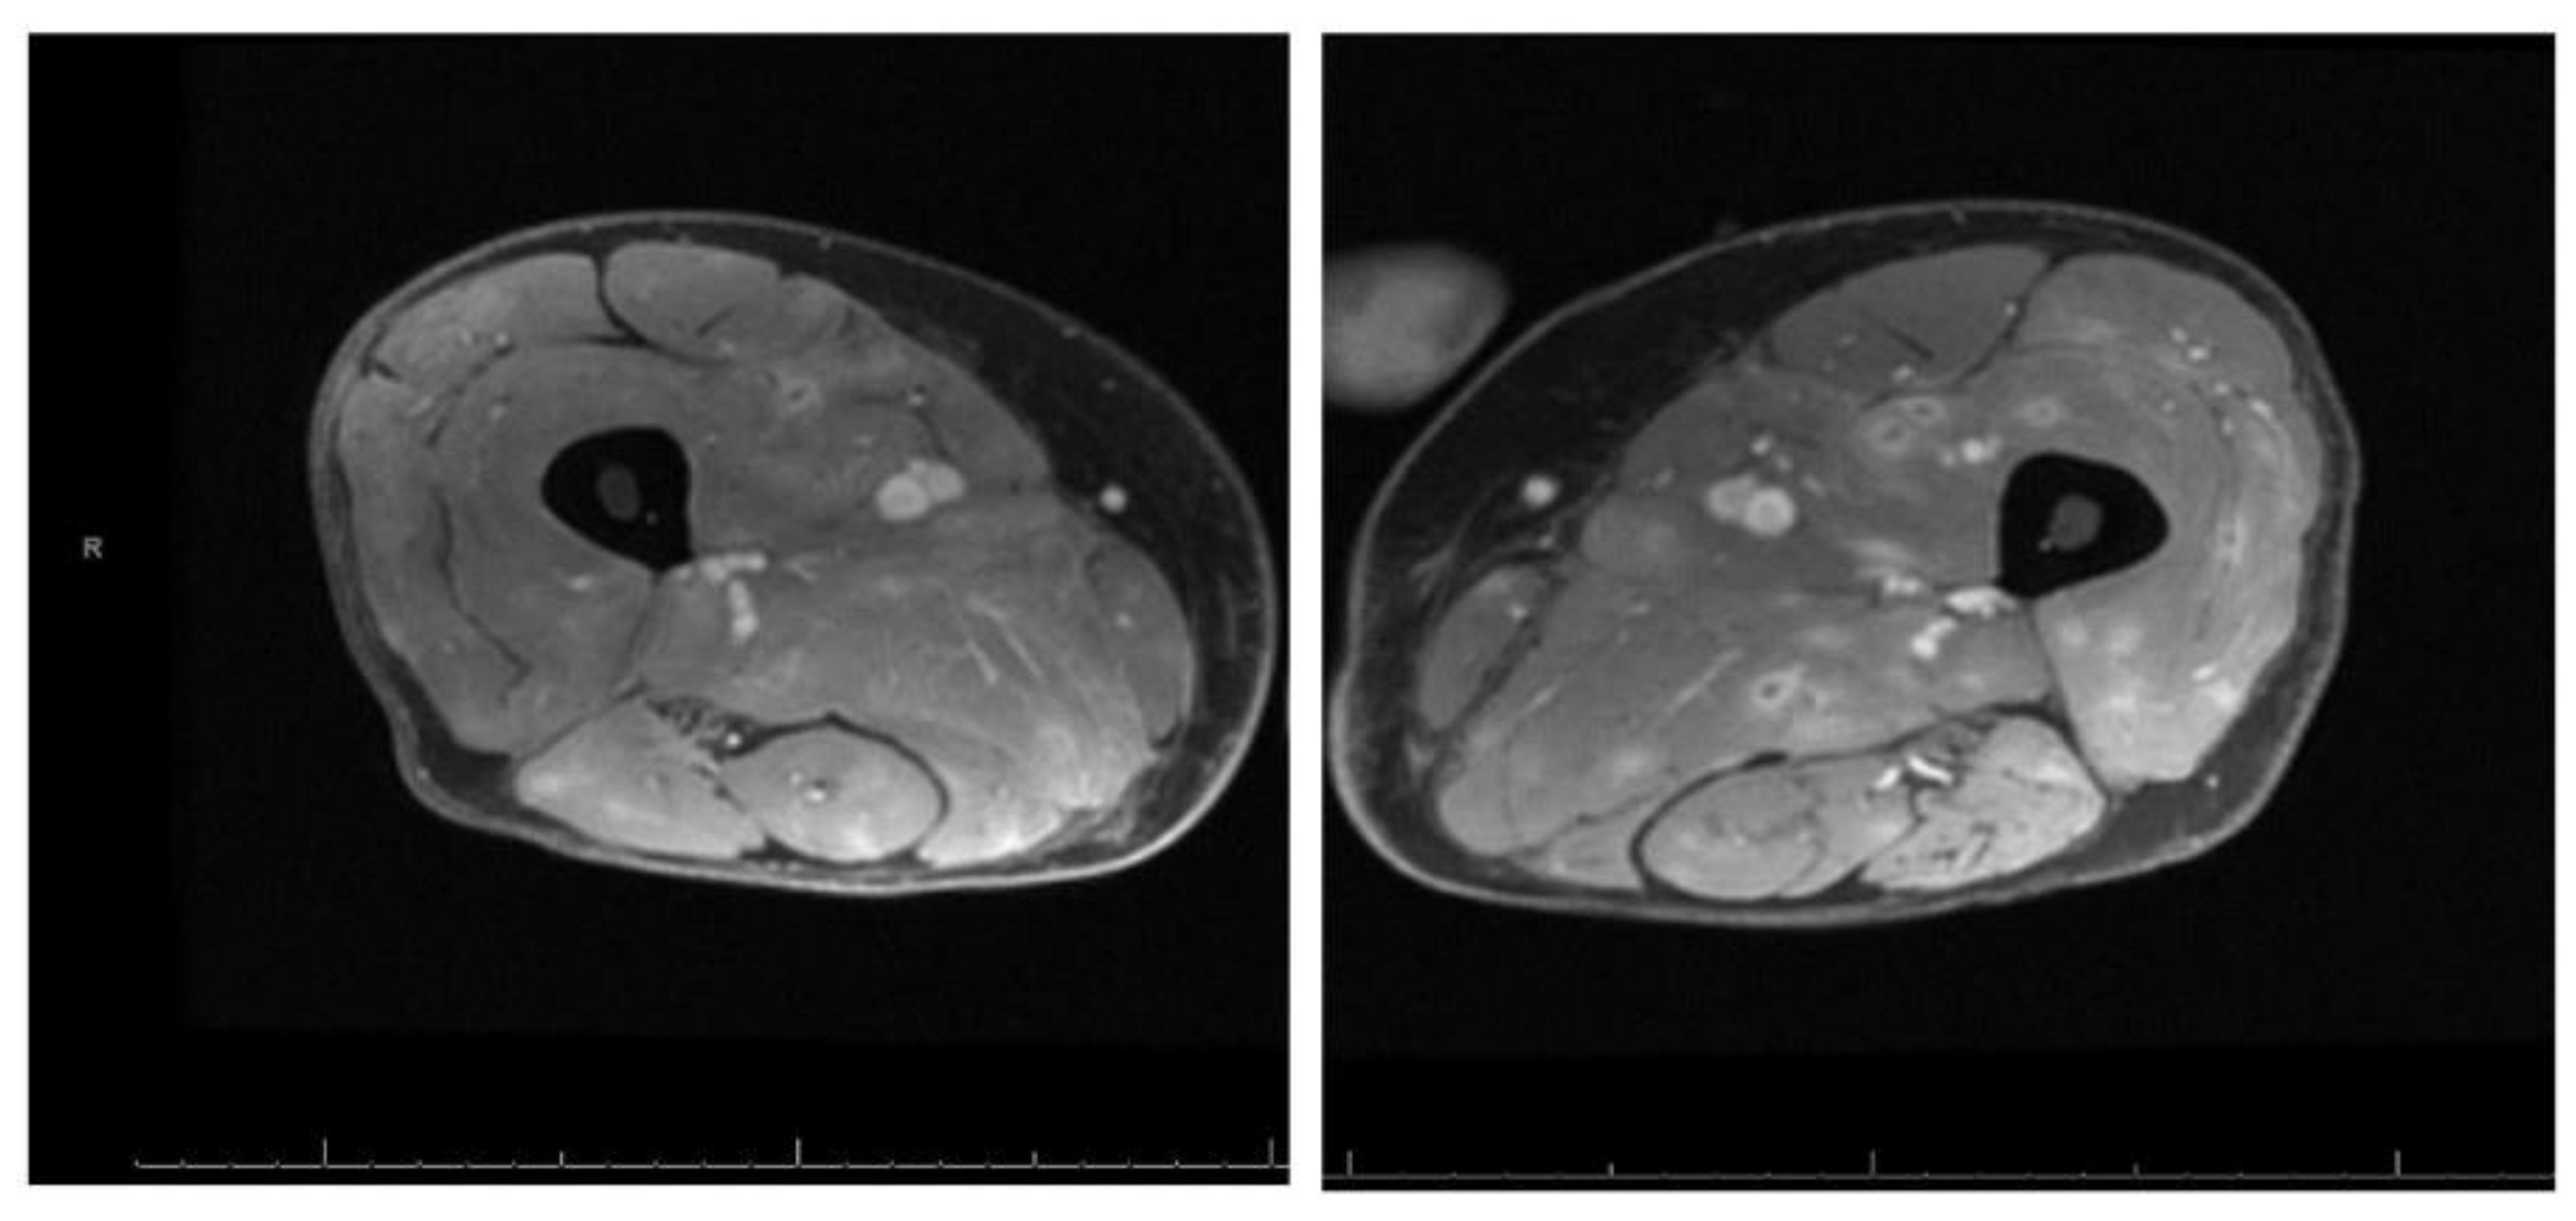

MRI of the bilateral thighs showed diffuse muscle edema with innumerable foci of nodular and ring enhancement-concerning for diffuse infectious myositis (Figure 1).

Figure 1. MRI of bilateral thighs with diffuse edema and multiple nodular and ring enhancing lesions.